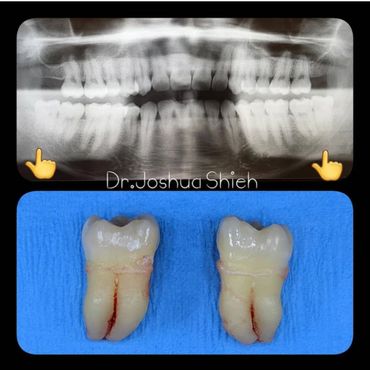

If the tooth is planned for extraction, an x-ray of the area will be taken to plan for the type of extraction.

Simple extractions are performed on erupted teeth that have regular anatomy (root and crown), and are not severely broken.

If you feel that your wisdom teeth are starting to cause problems, book an appointment to assess their condition, a panoramic x-ray will be taken and a thorough examination is conducted.